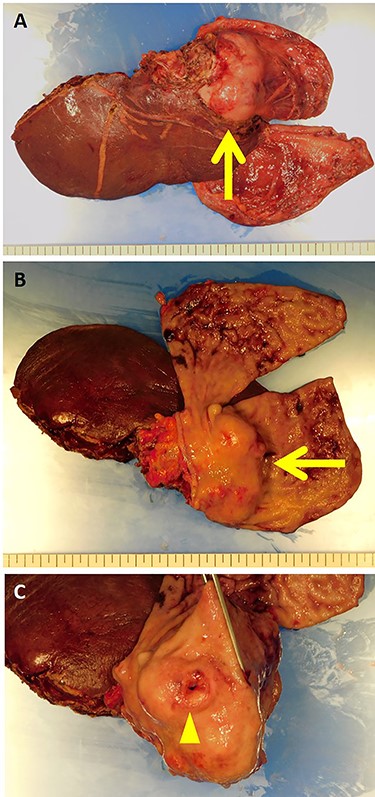

The patient was taken up for surgery. Intraoperatively, the tumor was located in the stomach wall at the cardia and was invading the liver directly (Fig. 3). We performed a lateral hepatectomy by the Glissonean pedicle ligation method, proximal gastrectomy and lymphadenectomy. The operation time was 3 h and 19 min, and intraoperative blood loss was 260 ml. The resected specimen showed a white solid tumor of dimensions 80 mm × 55 mm × 44 mm. It showed a little ulcerative change in the mucosal layer (Fig. 4). Most of the tumor originating from the liver was found under the gastric mucosa (Figs 4 and 5). Microscopically, a poorly differentiated adenocarcinoma with unclear duct formation was detected (Fig. 6). The non-tumor area of the liver was normal. Immunostaining showed that the tumor was positive for AE1/AE3 and negative for CK20, CK7, CD34, c-kit, CD56, synaptophysin and chromogranin A (Fig. 6). Based on these findings, our diagnosis was ICC with gastric infiltration, and we categorized it as pT4, pN0, cM0, Stage IIIB as per the eighth edition of the American Joint Committee on Cancer (AJCC)/Union for International Cancer Control (UICC) [2]. The immediate postoperative course was uneventful, and the patient was discharged on postoperative Day 16. Three months after the surgery, he was administered S-1 orally as adjuvant chemotherapy. However, 12 months after the surgery, multiple bone metastases were detected on CT. He underwent palliative radiation to relieve pain and prevent pathological fractures.

The resected specimen showed a white solid tumor continued from the left lateral liver to the stomach wall (A, arrow). Most of the tumor was found under the gastric mucosa (B, arrow). The tumor looked like a submucosal tumor with delle (C, arrowhead).

The tumor originated from the liver and showed extrahepatic growth (arrow).